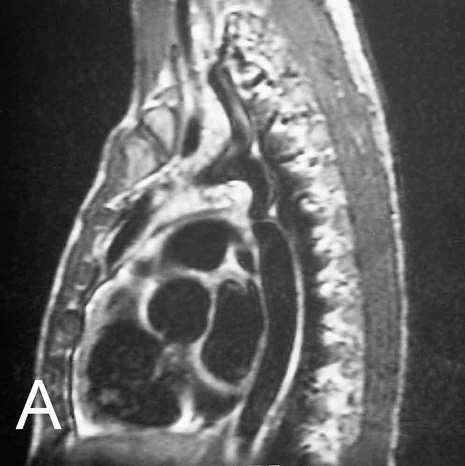

Image A is an unlabeled image from a T1-weighted sagittal MR of a patient with abnormalities of the intercostal arteries.

Image B shows the abnormal aorta, outlined in red, which has a marked narrowing just below the level of the ductus:  a coarctation.  In this condition, the intercostal arteries may become markedly enlarged as they serve as a collateral pathway for blood to get past the area of narrowing, as shown here.